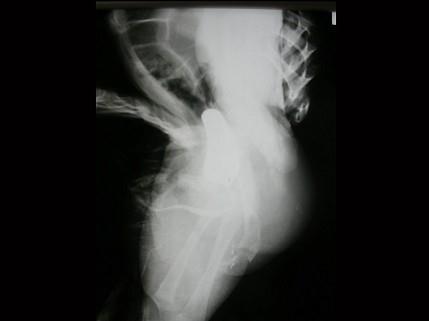

问题 男,4个月,阴茎、排尿异常4个月,行尿道造影如图所示,最可能的诊断是?(?)

选项 A.正常尿道 B.尿道瓣膜形成 C.尿道下裂畸形 D.尿道憩室 E.尿道重复畸形

答案 E